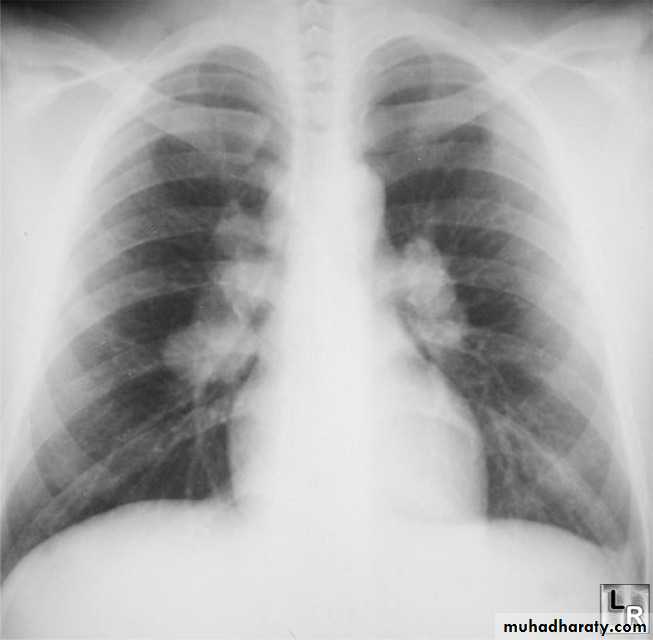

Radiographic featuresPlain film

Typical radiographic features of mitral regurgitation include :

frontal projection

1.left atrial enlargement

convexity or straightening of the left atrial appendage just below the main pulmonary artery (along left heart border)

2.double density sign: the right side of the enlarged left atrium pushes into the adjacent lung and creates an addition contour superimposed over the right heart

3.elevation of the left main bronchus and splaying of the carina

4.upper zone venous enlargement due to pulmonary venous hypertension

5.left ventricular enlargement is also eventually present due to volume overload

6.Features of pulmonary oedema may also be present.

Mitral valve disease